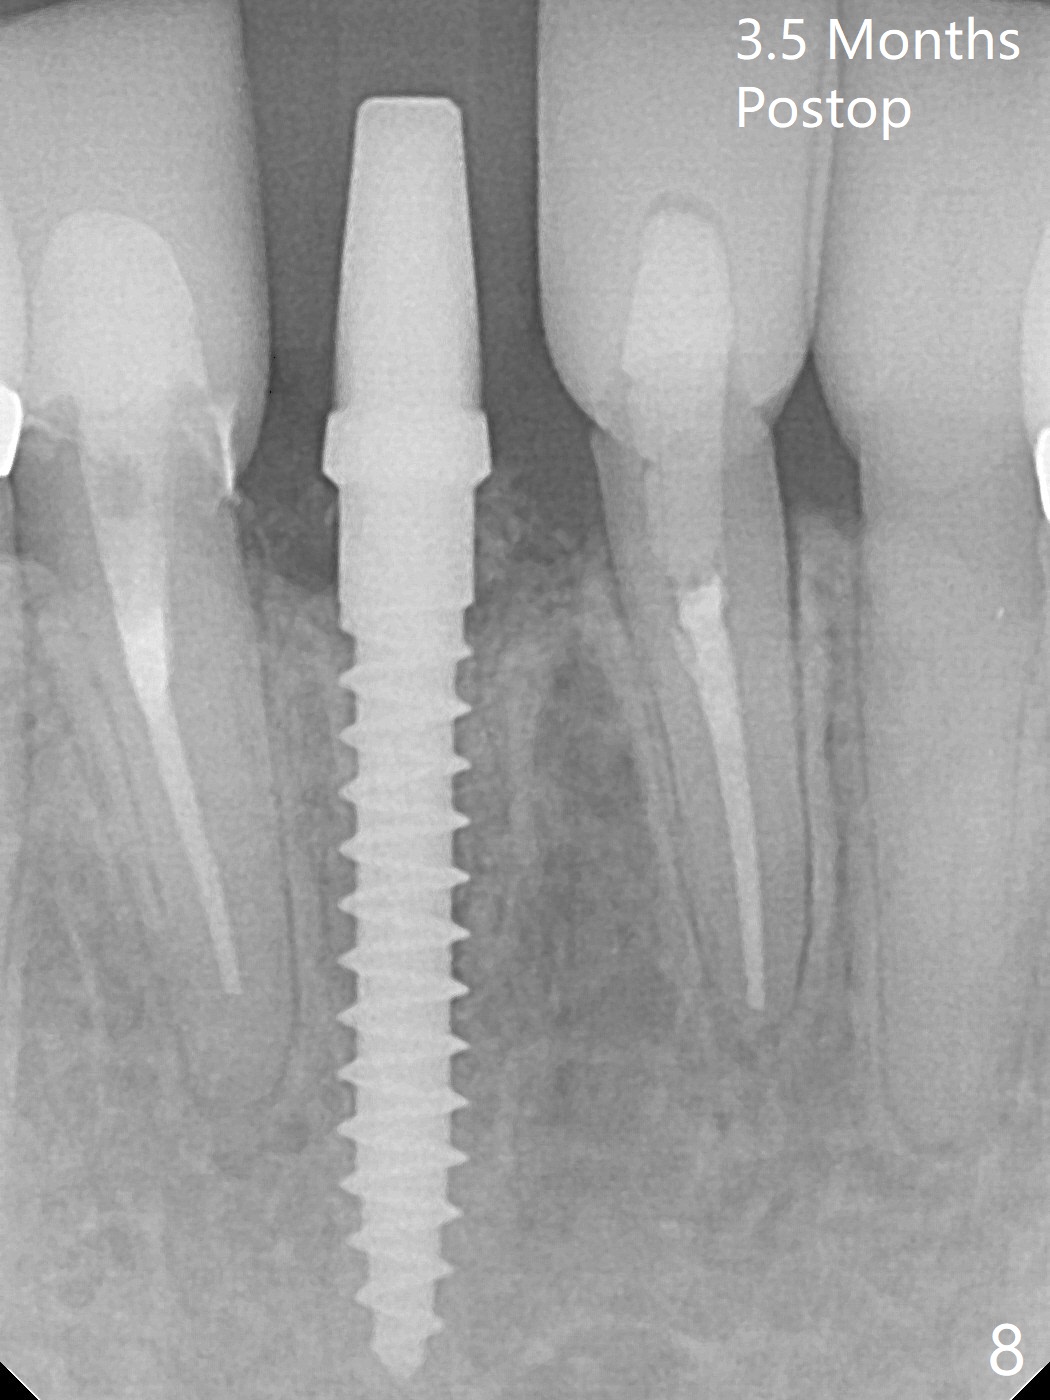

A drawback of implant planning at #25 is not to use a preop PA (Fig.1 (^ fracture line)). The initial trajectory seems to be alright (Fig.2), but a 2.5x14(2) mm implant placed is close to the tooth #26 (Fig.3). In fact the affected tooth is deviated distal; osteotomy should be initiated in the mesial slope of the socket (Fig.4 red line). The final trajectory appears to be perfect (Fig.5). Furthermore the 1st intraop PA should be analyzed carefully (Fig.6). A new osteotomy should be established mesial or the existing one should be moved mesial with Lindamann bur (Fig.7). The distal implant placement may be related to more bone loss in the distal crest 3.5 months postop (Fig.8) and more severe distal papillary recession (Fig.9 *). The bone density increases at the levels of the non-thread and thread portions of the implant (in the original socket) nearly 10 months post cementation (Fig.11 *, <). There is no bone loss 16 months post cementation (Fig.12).